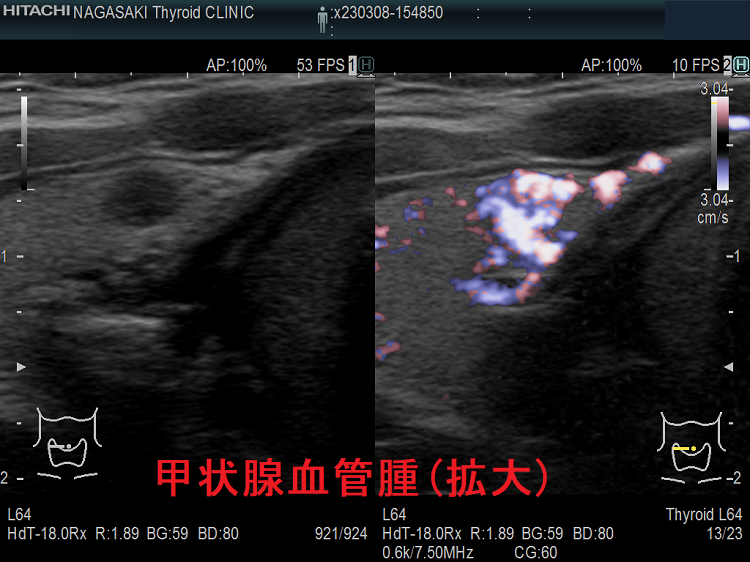

甲状腺に発生する血管腫は非常に稀で、日本の報告例もわずかです(日臨外会誌 72(3),579―583,2011)。

甲状腺血管腫(拡大) ドプラーモード(eFlow);腫瘍内血管が3次元的に見え、毛玉の様。